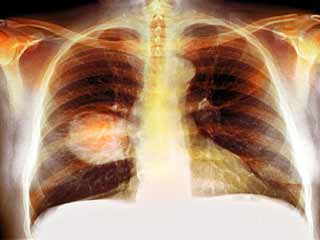

कैंसर, शरीर में कहीं भी असामान्य कोशिकाओं की अनियंत्रित वृद्धि है। स्तन कैंसर, त्वचा कैंसर, फेफड़ों का कैंसर, पेट का कैंसर, प्रोस्टेट कैंसर और लिंफोमा सहित 100 से अधिक प्रकार के कैंसर हैं। लक्षण प्रकार के आधार पर भिन्न होते हैं। इन असामान्य कोशिकाओं को कैंसर कोशिका, मैलिग्नैंट ट्यूमर या ट्यूमर कोशिकाएं कहा जाता है। ये कोशिकाएं शरीर के सामान्य ऊतकों में घुसपैठ कर सकती हैं। कई कैंसर और असामान्य कोशिकाएं जो कैंसर के ऊतकों (Tissues) की रचना करती हैं, उन्हें उस ऊतक के नाम से पहचाना जाता है, जो असामान्य कोशिकाओं से उत्पन्न हुआ है (उदाहरण के लिए, स्तन कैंसर, फेफड़े का कैंसर, कोलोरेक्टल कैंसर)। कैंसर उपचार में कीमोथेरेपी, विकिरण (Radiation) और सर्जरी शामिल हैं।

फेफड़ों का कैंसर (Lung Cancer) दुनिया भर में पुरुषों में होने वाला सबसे आम कैंसर था, 2018 में डाइग्‍नोज किए गए नए मामलों की कुल संख्या का 15.5% योगदान करते हैं। मुख्‍य रूप से तीन- फेफड़े, प्रोस्टेट और कोलोरेक्टल कैंसर, सभी कैंसर का 44.4% योगदान करते हैं (गैर-मेलेनोमा त्वचा कैंसर को छोड़कर)। इन आंकड़ों में 5% से अधिक योगदान देने वाले अन्य सामान्य कैंसर पेट और लिवर थे।

• फेफड़े का कैंस (20.9 लाख मामले)

• फेफड़े का कैंसर (17.6 लाख मौतें)